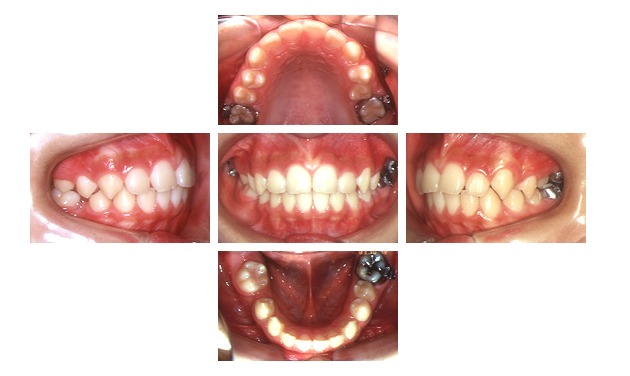

10歳10ヶ月

下顎前突(受け口)の二期治療

マルチブラケット装置により本格的な治療を開始しました

11歳0ヶ月

受け口が改善し、歯を抜くことなく受け口の治療が終了しました

14歳8ヶ月

下顎前突(受け口)の矯正治療が終わりました

- 年齢/性別

- 7歳/女児

- 主訴

- 受け口

- 治療方法

- 上顎骨の劣成長、下顎骨の過成長を伴う下顎前突症と診断し、一期治療としてリンガルアーチ、チンキャップ、二期治療としてマルチブラケット装置にて非抜歯で治療

- 治療の費用

- 一期治療代¥367,500(税込)

二期治療代¥420,000(税込) - 治療期間

- 7年6ヶ月

- リスク・副作用

- 治療上のリスクとして歯肉退縮、顎関節症、歯根吸収、カリエス、失活歯、根の露出、 骨隆起、劣成長、歯周病があります。また、治療には個人差があります。